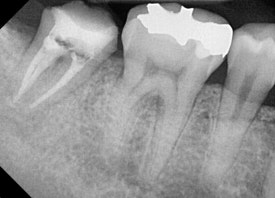

20250106

뿌리 끝에

까만 염증 주머니가 달렸습니다.

20250208

크라운을 제거해보니

얇은 금속 기둥이 하나 보입니다.

치과에서는 이를 포스트라고 부릅니다.

치아의 머리 부분이 많이 부족할 때,

뿌리에 이 기둥을 심어서

머리 부분을 지지해주는 역할을 합니다.

결론부터 말씀드리면

이번 재치료에서는 굳이 포스트를 식립하지 않았습니다.

그닥 필요해보이지 않아서요.